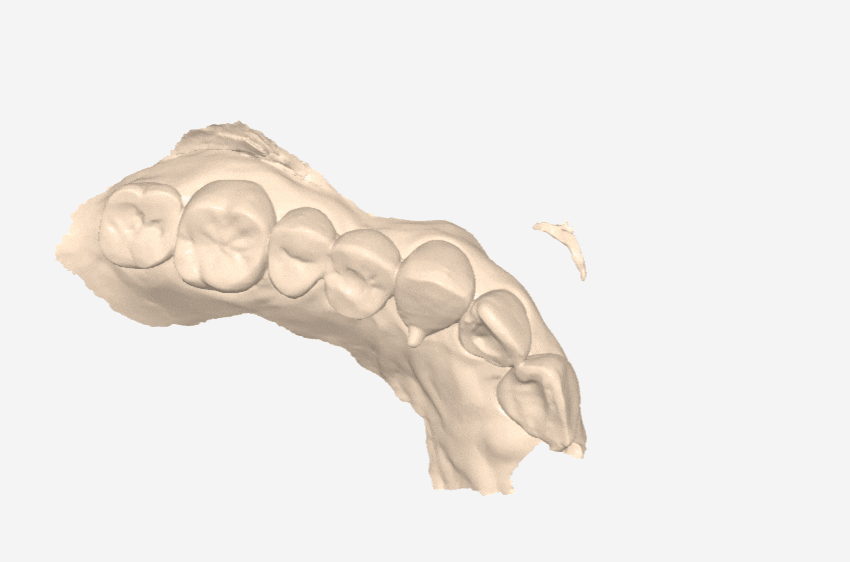

최근 아래 앞니가 나비 날개처럼 뻗어

고민이셨던 분이 찾아오셨습니다.

치아가 바깥으로 벌어져 있다 보니

평소 입술이 자꾸 걸리고

면 요리를 드실 때도 잘 끊기지 않아

무척 불편하셨다고 해요.

전체적인 치아 배열은 안정적이라,

앞니를 많이 깎아내지 않고도

충분히 배열을 맞출 수 있는 상태였습니다.

전체 치아를 이동시키는 교정 대신,

틀어진 각도만 정교하게

바로잡는 라미네이트로 가닥을 잡았고,

결과적으로 환자분께

가장 만족스러운 대안이 되었습니다.

살짝 틀어져 있던 앞니가 제 자리를 찾고 나니,

미소가 훨씬 단정하고 편안해 보이시죠?